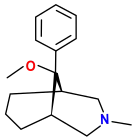

Benzomorphans

- 5,9 alpha-diethyl-2-hydroxybenzomorphan (5,9-DEHB)

- 8-Carboxamidocyclazocine (8-CAC)

- Alazocine

- Anazocine

- Bremazocine

- Butinazocine

- Carbazocine

- Cogazocine

- Cyclazocine

- Dezocine

- Eptazocine

- Etazocine

- Ethylketazocine

- Fedotozine

- Fluorophen

- Gemazocine

- Ibazocine

- Ketazocine

- Metazocine

- Moxazocine

- Pentazocine

- Phenazocine

- Quadazocine

- SKF-10047

Structures

| Benzomorphans | ||||